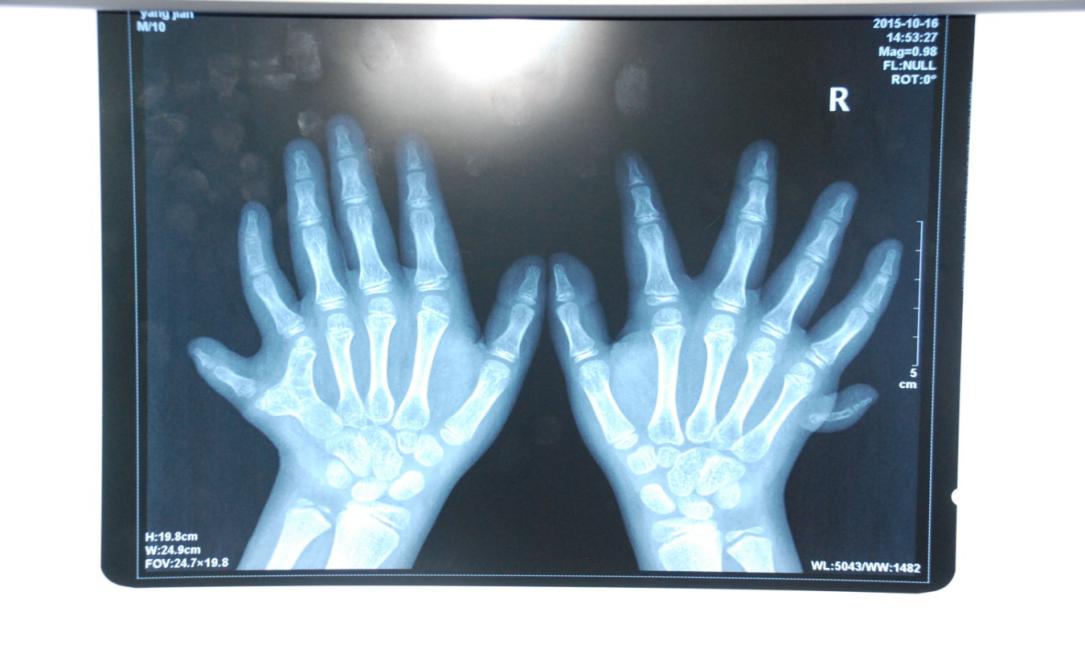

廈門(mén)眼科中心小兒眼科修陽(yáng)暉博士在日常的診療過(guò)程中就接診了不少這樣的的特殊家庭,讓其尤為印象深刻的就是一年前接診的BBS綜合征患者。當(dāng)時(shí)來(lái)院就診的是一對(duì)親兄弟,之前已在多家醫(yī)院做過(guò)檢查,因其均有較大散光和斜視,肉眼下眼底檢查未見(jiàn)異常,故外院均診斷為弱視,這也符合眼科門(mén)診常規(guī)的診斷邏輯與思維。但由于兄弟倆均有智力發(fā)育遲緩、特殊面容及四肢均有六指和六趾的特異體征引起了修陽(yáng)暉博士的警覺(jué):會(huì)不會(huì)是一種特殊遺傳性疾病或綜合征?后續(xù)的檢查結(jié)果進(jìn)一步證實(shí)了修陽(yáng)暉博士的懷疑---患兒均有夜盲,ERG、VEP及OCT檢查顯示雙眼的視網(wǎng)膜神經(jīng)上皮層結(jié)構(gòu)及功能均明顯異常。由于之前未遇到此種病例,修陽(yáng)暉博士在診斷一欄寫(xiě)下視網(wǎng)膜色素變性并打上了個(gè)問(wèn)號(hào),同時(shí)留下了病人的聯(lián)系方式。

BBS綜合征(Bardet-Biedl綜合征)是一種主要累及纖毛結(jié)構(gòu)與功能的罕見(jiàn)常染色體隱性遺傳性疾病。纖毛分布于哺乳動(dòng)物體內(nèi)的大多數(shù)細(xì)胞,它是一種廣泛存在于各種細(xì)胞表面的細(xì)胞器,體型微小但結(jié)構(gòu)復(fù)雜、作用強(qiáng)大,能感知細(xì)胞外機(jī)械和化學(xué)信號(hào)變化并協(xié)助其轉(zhuǎn)導(dǎo)到細(xì)胞內(nèi)部從而引起細(xì)胞應(yīng)答。高等動(dòng)物的視覺(jué)、觸覺(jué)、嗅覺(jué)、聽(tīng)覺(jué)的傳遞都依賴于體內(nèi)外正常的纖毛結(jié)構(gòu)和功能。因此BBS綜合征常累及全身多個(gè)系統(tǒng)和器官,在臨床上主要表現(xiàn)為:視網(wǎng)膜色素變性、智力發(fā)育異常、向心性肥胖、多指(趾)、性腺發(fā)育異常、腎臟異常。除此之外還有許多諸如:語(yǔ)言發(fā)育障礙、聽(tīng)力異常、嗅覺(jué)異常、斜視、白內(nèi)障、散光、牙齒發(fā)育異常、短指(趾)、并指(趾)、肝纖維化、糖尿病、高血壓等表現(xiàn)。